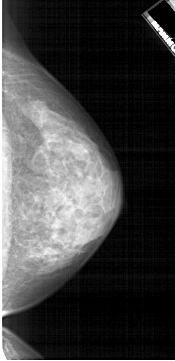

A_1914_1.LEFT_MLO

LEFT_MLO LINES 5326 PIXELS_PER_LINE 2446 BITS_PER_PIXEL 12 RESOLUTION 43.5 OVERLAY